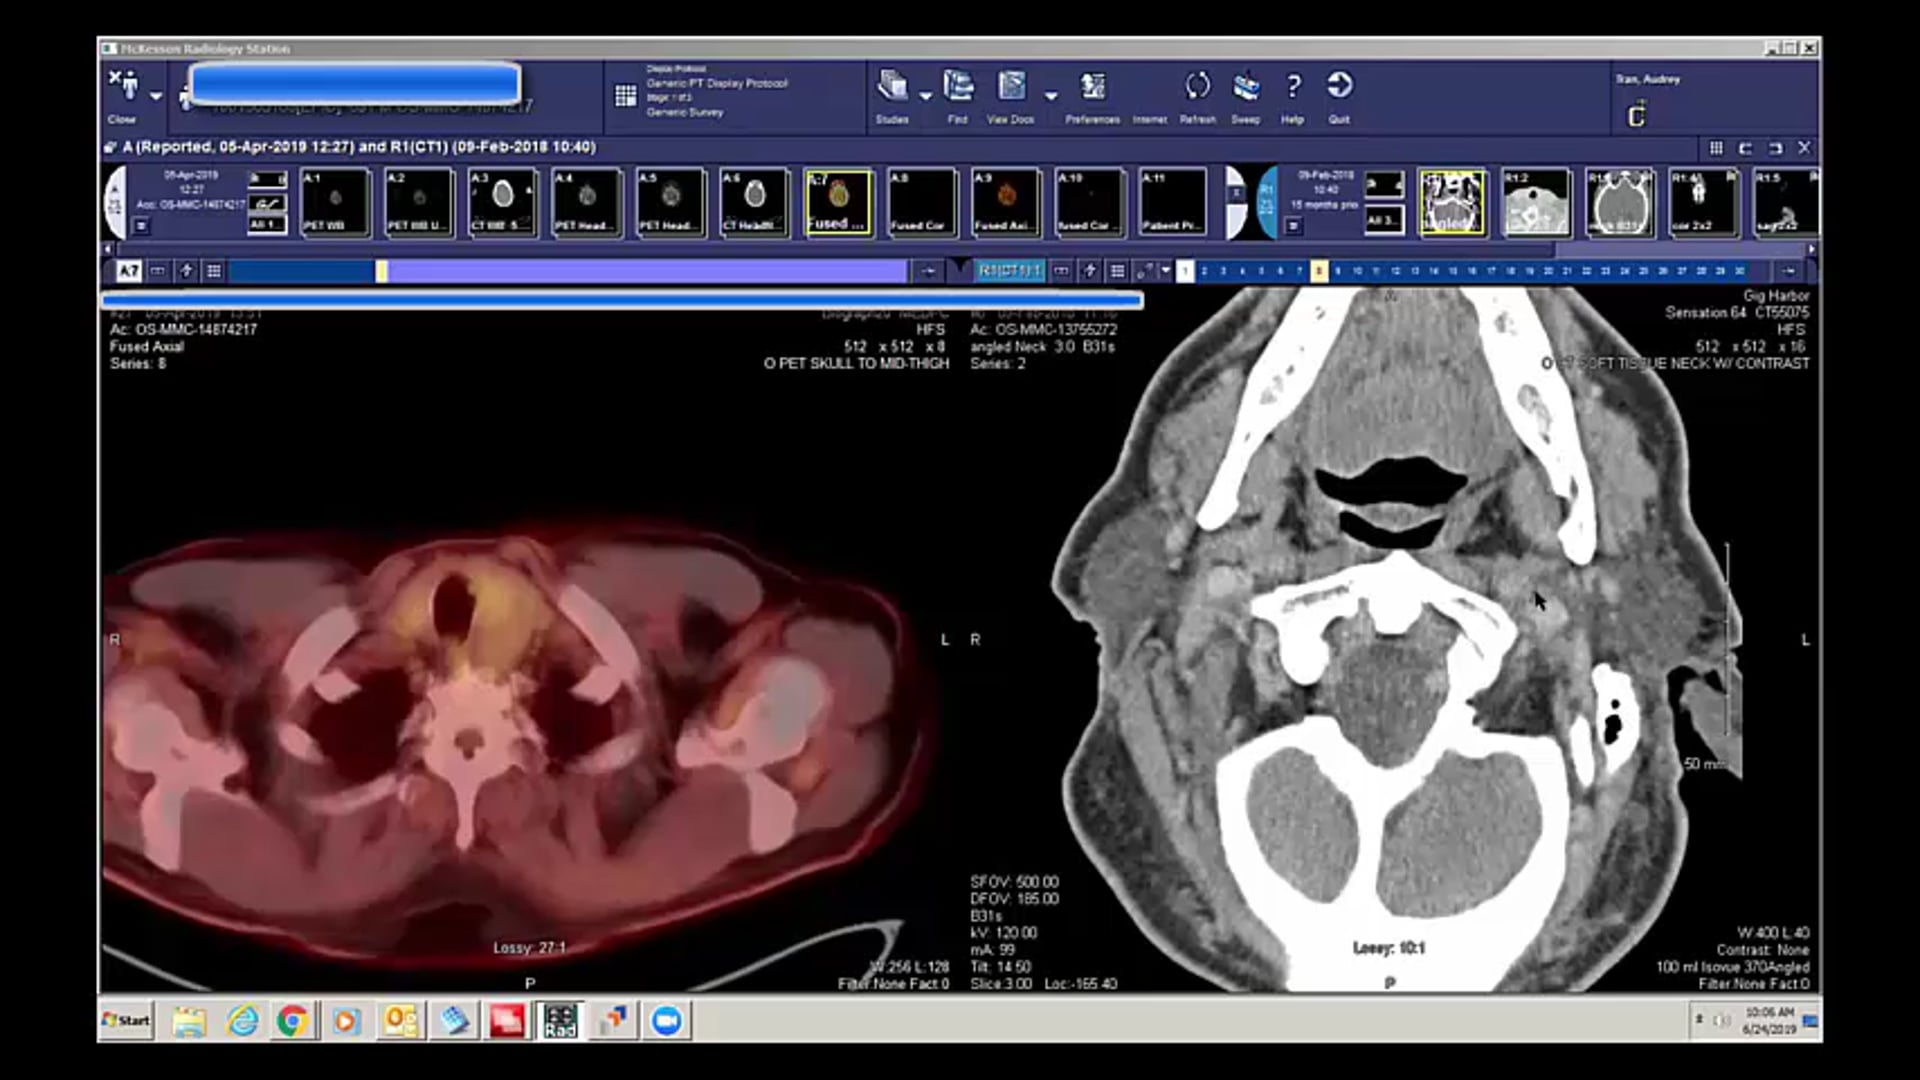

06/24/19 - Dr. David Sher - Radiation Oncology - Head and Neck US